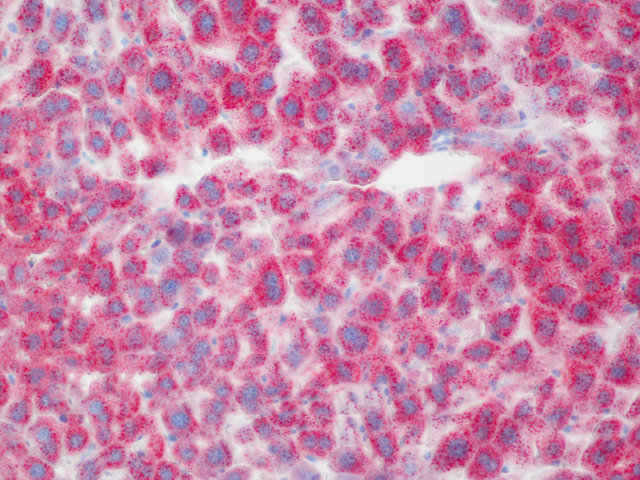

脂滴呈橘红色至鲜红色;细胞核呈深蓝色。

样片参考: